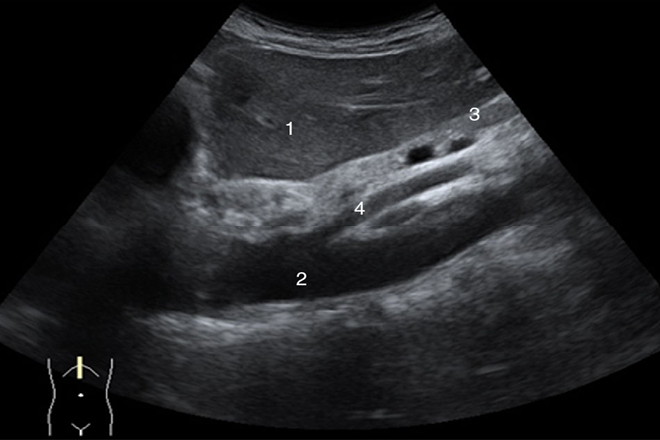

REFERENCIAS ANATÓMICAS VASCULARES para localizar la anatomía del páncreas:

• CABEZA: anterior a la vena cava inferior, cuando están en decúbito lateral izquierdo se desliza y se encontrara anterior a la aorta.

• CUERPO Y COLA: anteriores a la vena esplénica.

• TRIFURCACIÓN DEL TRONCO CELIACO: se sitúa superior al páncreas.

• ARTERIA ESPLÉNICA: corre paralela al aspecto superior del páncreas.

• ARTERIA GASTRODUODENAL: se origina de la arteria hepática común  y se dirige inferiormente sobre las caras anterior y lateral  de la cabeza pancreática.

• VENA MESENTÉRICA SUPERIOR: posterior del cuello y cuerpo y medial de la cabeza del páncreas.

1. CONDUCTO PANCREÁTICO PRINCIPAL

Se visualiza como una delgada línea sonolucente de unos 3mm paralela al eje mayor de la glándula limitada  por 2 líneas hiperecogénicas que corresponden a sus paredes

Se visualiza mejor  en el cuerpo.

Se ve medial  al conducto  colédoco distal y no debe de confundirse con el colédoco o un conducto cístico.

En las imágenes transversales  se confunde con la pared  hipoecogénica  de la superficie  posterior del estómago y se evita  explorando el plano sagital en el que se observa la pared posterior del estómago en continuidad con el resto de la pared gástrica.